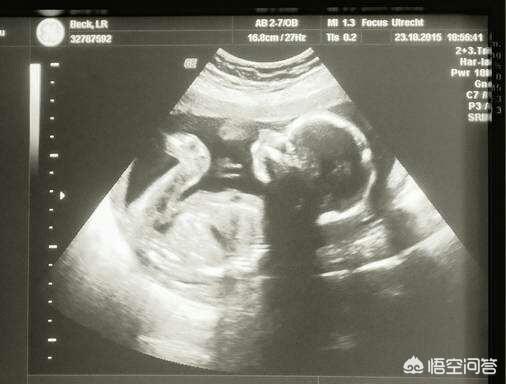

Tatsächlich aber verbessert der 4D-Ultraschall die diagnostische Wirksamkeit im Vergleich zum normalen Ultraschall nicht, und die allgemeinen öffentlichen Krankenhäuser führen keine 4D-Ultraschalltestprogramme durch.

3D oder 4D ist kein Faktor, der die Ergebnisse der Ultraschalluntersuchung beeinflusst, die Erfahrung des Ultraschallarztes ist der wichtigste Faktor.

Der Ultraschall ist das Auge des Geburtshelfers und des Gynäkologen. Es stimmt, dass die Genauigkeit des Ultraschalls aus vielen Gründen wie dem Einfluss der Lage des Fötus, den Unterschieden in der fötalen Schwangerschaft, den Unterschieden in der Dicke der Bauchdecke der Schwangeren und den Unterschieden in der Art der fötalen Erkrankungen stark eingeschränkt ist, aber das Ultraschallscreening auf fötale Fehlbildungen ist immer noch zu 50 bis 70 % genau. Das bedeutet, dass mehr als die Hälfte der missgebildeten Babys durch Ultraschall rechtzeitig erkannt wird.